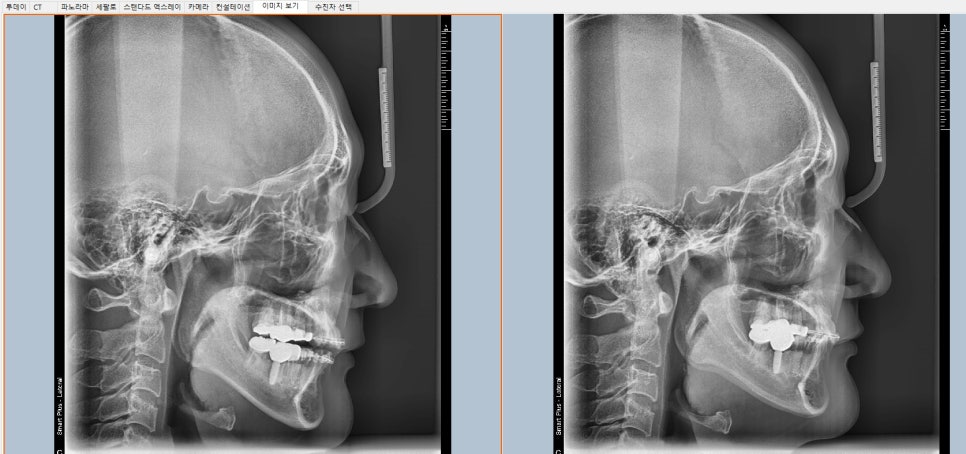

위 사진을 자세히 비교해 보세요.

무엇이 다른가요?

대부분 치아교정은 돌출입이나 비뚤어진 치아에 교정을 하는데 역교정은 위 사진처럼 합죽이 입에 교정하는 방법입니다

사진 보시면 헷갈리시겠지만 오른쪽이 비포이고, 왼쪽이 중간과정 입니다

오른쪽 앞니를 보시면, 앞니 각도가 안쪽으로 많이 들어와있습니다.

이미 3달 정도 진행했을때 찍은사진이구요, 많이 좋아지긴 했지만 아직도 옥니상태입니다.

그에 비해서 왼쪽사진(환자분이 입을 좀 벌리고 찍긴했습니다 ㅠㅠ) 은 앞니 각도가 앞으로 더 나와있군요,

위에 앞니만 앞으로 꺼낼수는 없기때문에

아래 앞니도 앞으로 내밀었는데요

그에 대한 결과로, 왼쪽 사진은 아래 입술 아래쪽 커브를 보시면, 오른쪽 사진 보다 입술아래쪽 커브가 더 얕아져서

아래 입술의 합죽함이 많이 개선되어있음을 보실수 있습니다.

결과적으로 턱끝이 덜 튀어나와보이는거죠.